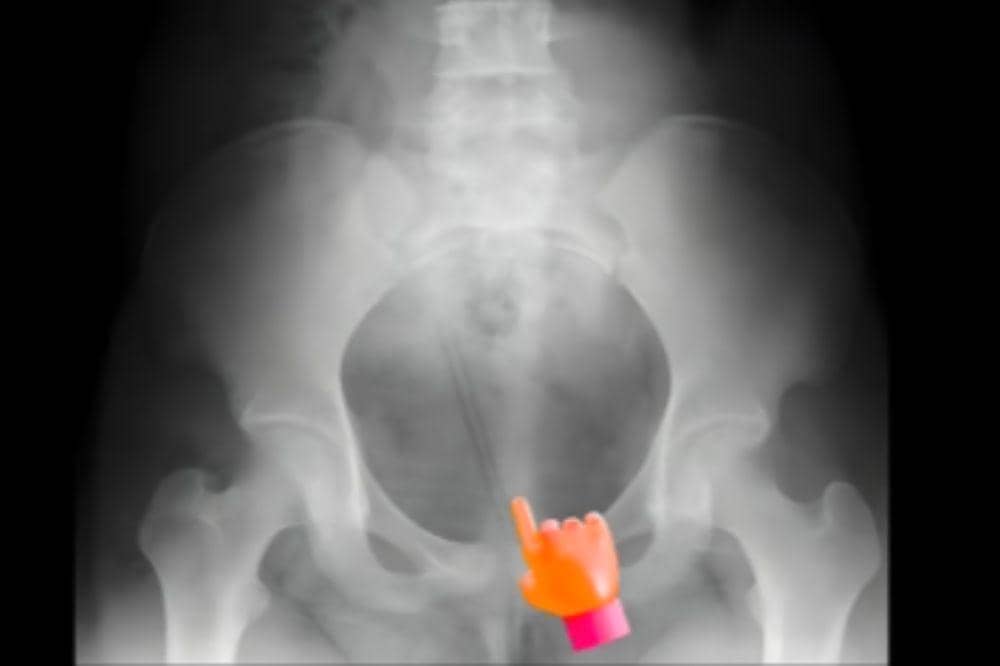

Sebuah cerita memilukan dibagikan oleh dr. Ryuu Damara Parisudha, Sp.U, Dokter Spesialis Urologi. Dalam Instagram pribadinya ia mendapati pasien remaja perempuan 12 tahun dengan pensil di dalam kandung kemihnya.

Dalam unggahannya, dr. Ryuu menjelaskan kronologi medis yang terjadi pada pasien berusia 12 tahun tersebut. Awalnya, sang anak mencoba memasukkan sebuah pensil ke area kemaluannya karena ajakan atau paksaan dari lingkungan pergaulannya.

Tanpa disadari, pensil tersebut masuk melalui saluran kencing bawah dan terdorong lebih dalam hingga mencapai kandung kemih.